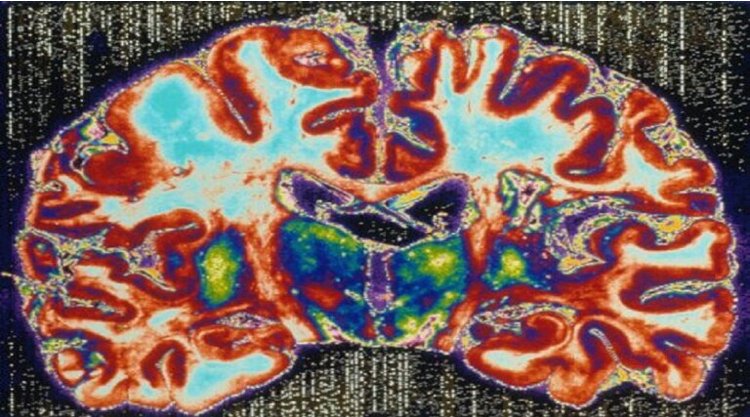

اكتشاف نوع جديد من مرض الفصام بحجم دماغ حقيقي

اكتشف علماء من جامعة بنسلفانيا الأمريكية خلال تحليلهم صور مسح الدماغ لـ 300 مصاب بانفصام الشخصية، نوعين فرعيين منفصلين من المرض.

وتفيد مجلة “الدماغ” بأن العلماء اكتشفوا أن النوع الأول يتميز بانخفاض حجم انتشار المادة الرمادية مقارنة بالأشخاص الأصحاء، في حين كان للنوع الثاني حجم مماثل لحجم الدماغ الطبيعي. وهذا يشير إلى أن أخذ هذا الاختلاف بالاعتبار سيساعد على وصف خيارات علاج فردية أكثر فعالية.

ويقول البروفيسور كريستوس دافاتسيكوس ، كبير الباحثين من جامعة بنسلفانيا، “أظهرت دراسات عديدة، أن حجم دماغ الأشخاص المصابين بانفصام الشخصية، هو أصغر من حجم دماغ الأصحاء. ولكن لم يكن هذا صحيحا لدى ثلث المرضى الذين خضعوا لهذه الدراسة، حيث كان حجم دماغهم طبيعيا”. وأضاف، مستقبلا لن نقول “إنه مصاب بانفصام الشخصية” بل سنقول “”المريض لديه” نوع فرعي “أو” نمط مرضي “، وليس لديه مثل هذه المظلة الواسعة”.